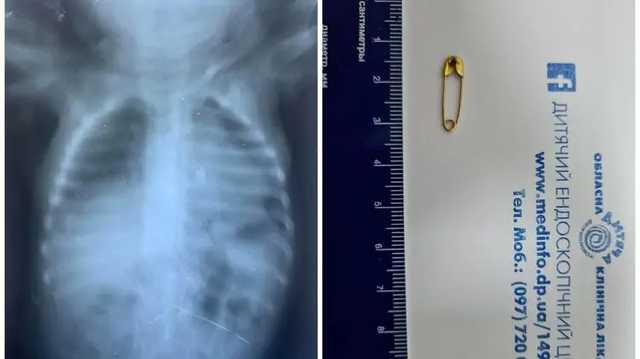

В Днепре врачи спасли ребенка, который вдохнул булавку. Ребенок попал в больницу в тяжелом состоянии. Об этом сообщил детский эндоскопический центр в Facebook.

Малыш, которому нет и годика, вдохнул булавку во время игры. Ребенку провели дополнительное обследование. После чего под общим обезболиванием при проведении бронхоскопии извлекли инородное тело.

Отмечается, что в настоящее время ребенок дома в удовлетворительном состоянии.